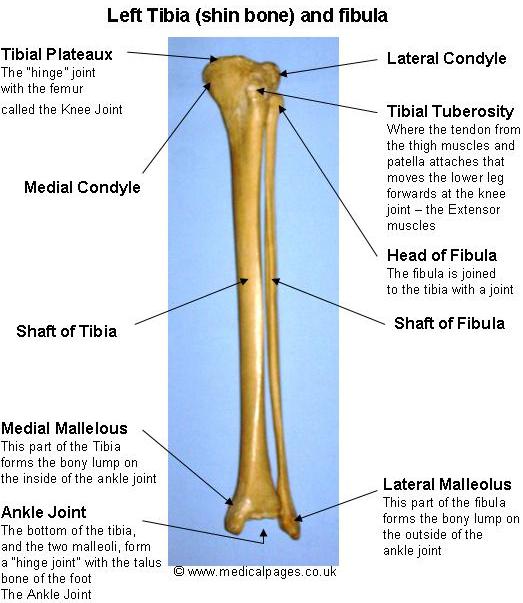

differences between the tibia and fibula – Google Search | Anatomy and …

Bone Parallel To Fibula

Tibia (shaft) and Fibula (shaft) Work Bulletin Boards, Skeleton Anatomy …

Anatomy Tibia And Fibula Diagram | MedicineBTG.com

Tibia And Fibula Anatomy